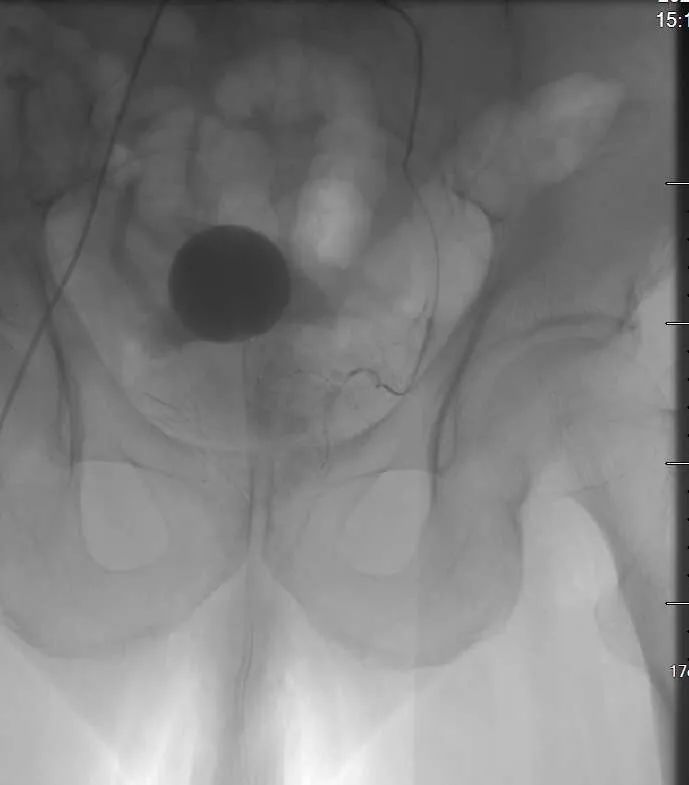

患者在局部麻醉下经股动脉穿刺,引入导管至前列腺的供血动脉,注入栓塞微粒,阻断前列腺腺体的血液供应,使增生的前列腺因缺血萎缩而体积缩小,解除对尿道的压迫及下尿路梗阻,使排尿恢复顺畅。一般栓塞治疗 3 天左右即可拔除导尿管,恢复正常排尿。介入栓塞治疗具有创伤小、痛苦少、并发症少、恢复快等优点,且术前、术后饮食正常,穿刺点压迫 2 小时~4 小时即可下床自由活动。值得临床推广应用。